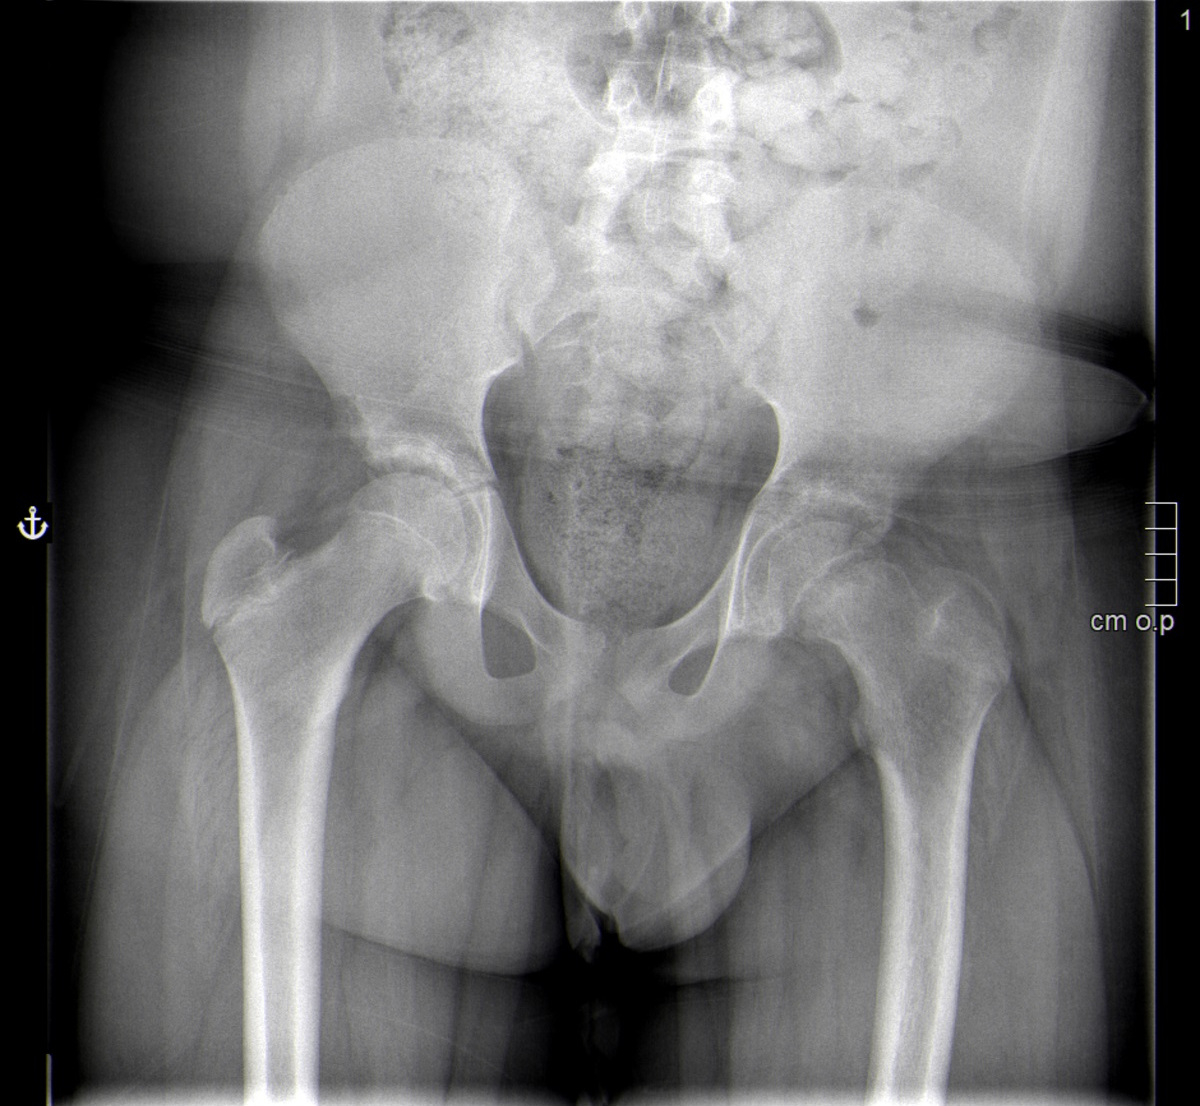

Paciente de 13 años que consulta por una dudosa sensación de disnea. Afebril, sin clínica de enfermedades infecciosas. A la exploración destaca obesidad y ausencia de signos de distrés respiratorio, con auscultación cardiopulmonar normal. Llama la atención una marcha antiálgica del paciente, que precisa la ayuda de muletas. Por anamnesis dirigida refiere gonalgia izquierda de mes y medio de evolución coincidente con un papiloma en el pie contralateral. En la exploración de los miembros inferiores presenta una marcada limitación a la rotación interna y la flexión de la cadera izquierda, con exploración de la rodilla normal. Se realiza radiografía de pelvis en proyección anteroposterior (Figura 1) y oblicua (Figura 2).

Figura 1. Radiografía de pelvis en proyección anteroposterior.